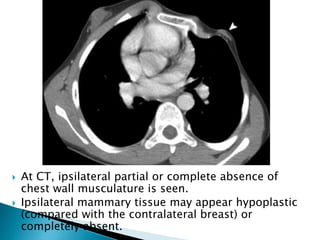

 At CT, ipsilateral partial or complete absence of

 Ipsilateral mammary tissue may appear hypoplastic

completely absent.